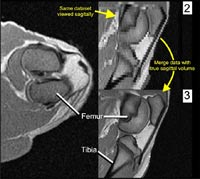

The limb, now embedded in a foam block, was then scanned in CT and MRI at O'Bleness Memorial Hospital in Athens, Ohio. The CT scans were performed on a GE HiSpeed Fx-i Helical CT scanner (120.0 kV, 100.0 mA, axial slice thickness of 1 mm). MR imaging was performed on a 1.0T GE Signa Short-Bore MRI system (T1, axial and sagittal slice thickness of 3 mm). The entire hindlimb was CT scanned, but the MR field of view was limited to the knee region. The scan data were then imported into a computer workstation, and analyzed using Amira 3.1 (TGS, Inc., San Diego). Because the 3mm slice thicknesses of the MRI datasets are rather coarse for generating 3D models, the axial and sagittal MR datasets were combined and resampled to produce a composite volume of 1mm intervals (Figure 3). |